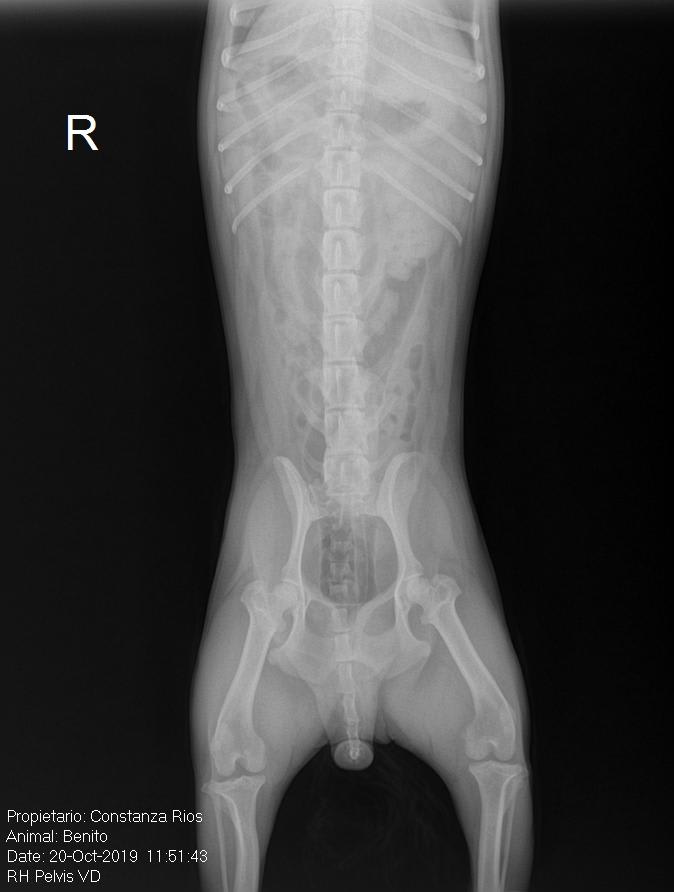

Pet's info: Dog | Maltipoo | Male | neutered | 6 years and 4 months old | 11 lbs

Hi, my dog has been suffering a back pain which I identified once I took him and he shouted. I took him to the vet and they gave him 3 days with anti-inflammatories but once the 3 days passed the pain came back. I took him to the vet again and they gave him 6 days with anti-inflammatories again. We are in day 5 and he has been relatively great but now the pain is coming back since he doesn't want to use the stairs for example. I will attach his x rays.

Poor Benito! When pets don't respond as well to anti-inflammaorties, I often try them on steroids (for 2-4 weeks), muscle relaxers and opioid pain medication. During this time, Benito should be crated at all times, allowed outside on a leash only to potty because you MUST make sure he is not moving around too much. You may also look into acupuncture or laser therapy which can also help significantly. Benito should be examined every 2 weeks until he is back to normal. The medications may need to be adjusted based upon his response. I hope this helps and that he feels better quickly.